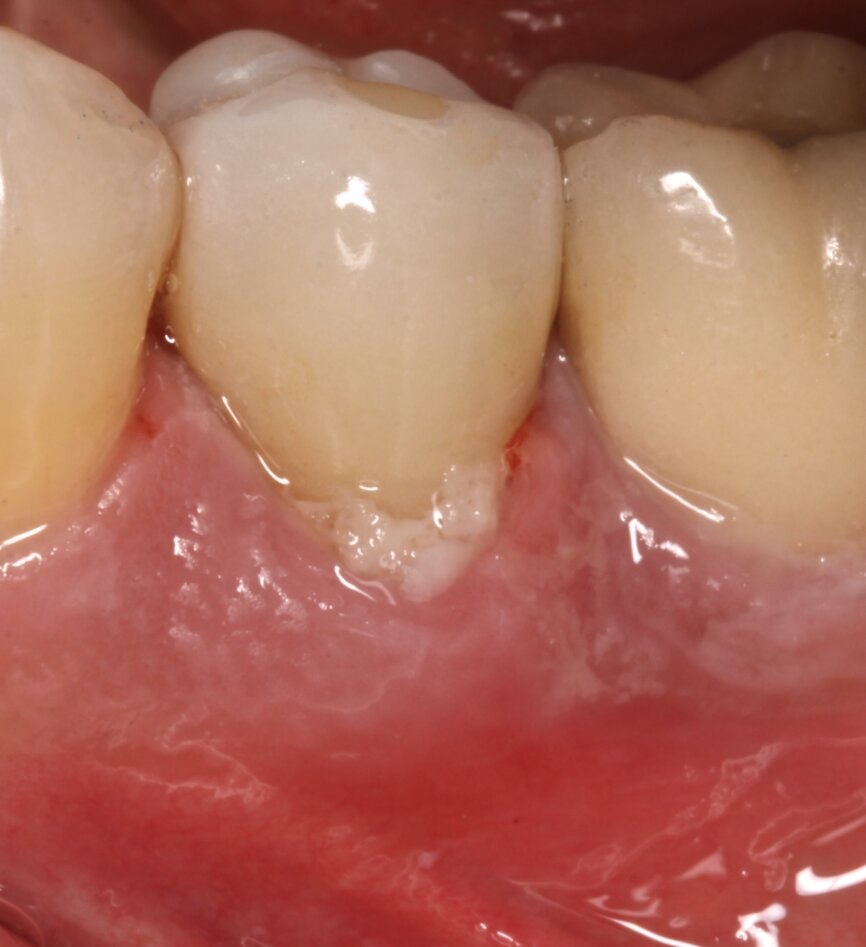

At the one-year follow-up visit, the soft-tissue contours adjacent to the implant restoration and the buccal bone volume and convexity still resembled those adjacent to the natural teeth. Bone levels around the implant appeared stable during radiographic evaluation (Fig. 9). No perceptible loss occurred. The artificial crown had an emergence profile mimetic of that of a natural tooth. At the two-year follow-up visit, the tissue contours looked stable and appeared even to have improved when compared with the one-year follow-up visit (Fig. 10).

The two-year follow-up postoperative cone beam computed tomography (CBCT) scan (Figs. 11 & 12), as well as the clinical photographs, illustrated the bone level, the buccal bone volume achieved and maintained over the period. Also, it was possible to see that the gap distance, radiographically, appeared to have been filled with bone. It was surprising also to see that bone level was well above the implant–abutment junction, maybe in response to a very efficient maintenance of a zero micro-gap at the junction owing to this BioBlock (BTI Biotechnology Institute) one abutment, one time concept, providing a virtual one-piece implant.

Fig. 13: Clinical situation two years after treatment.